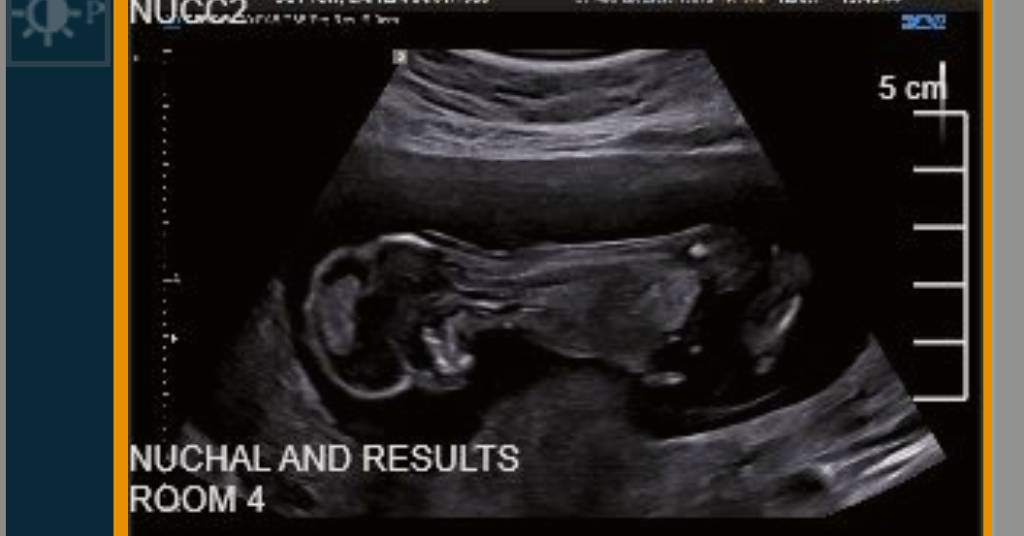

Unfortunately potty shots at 13 weeks aren't reliable and that's why the tech woudln't give an opinion. Do you have any nub shots (taken from the side?)

I agree with Atomic. You need a side shot.